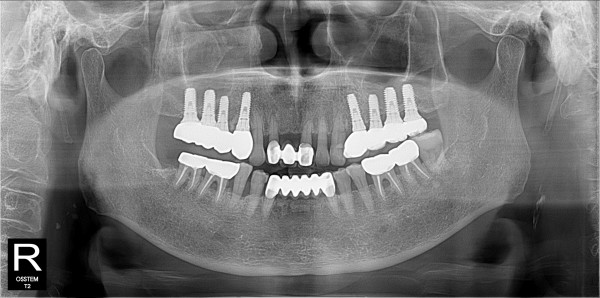

구치부 임플란트 최고관리자 0건 23-11-07 18:30 본문 구치부 임플란트 + 전치부 크라운 목록 이전글구치부 임플란트 23.11.07 다음글구치부 임플란트 23.11.07 댓글목록 0 댓글목록 등록된 댓글이 없습니다.